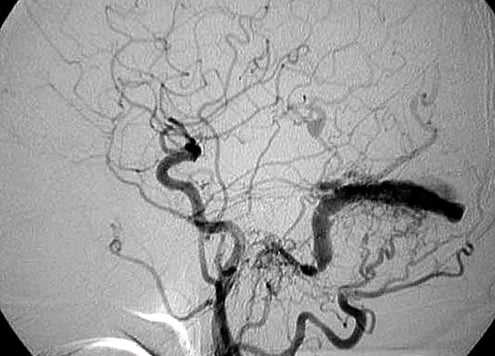

Проводят ли ангиографию сосудов мозга

- Одна питающая артерия, несколько питающих артерий или фистула, возникающая непосредственно из крупной артерии, например, из внутренней сонной артерии.

- Они часто кровоснабжают дуральный синус через диффузную сосудистую сеть, что приводит к его преждевременному контрастному усилению

- В зависимости от типа фистулы также наблюдается контрастное усиление кортикальных вен или верхней глазной вены

Бесконтрастная компьютерная томография (КТ) головного мозга эффективна только в диагностике неблагоприятных исходов ДАВФ — кровоизлияний и отека мозга, однако КТ-ангиография способна идентифицировать измененные артерии и вены, выраженную сосудистую сеть в дуральном синусе или мозговых оболочках, тромбоз венозного синуса. В ряде случаев аномальная перестройка сосудистой сети может быть скрыта артефактами, исходящими от костей черепа. Используя алгоритмы реконструкции для удаления костных структур на изображениях, недостатки исследования могут быть устранены [12, 21]. Однако «золотым стандартом» диагностики ДАВФ остается цифровая субтракционная ангиография [2, 10]. Благодаря высокому пространственному и временному разрешению катетерная ангиография позволяет получить информацию о расположении и анатомических особенностях соустья, идентифицировать важные особенности ДАВФ, такие как наличие кортикального рефлюкса, обструкции венозного оттока, аневризмы [9, 15, 19].

Проведенное дуплексное сканирование сосудов головы обнаружило признаки артериовенозной мальформации в бассейне левой наружной сонной артерии с артериализацией и усилением кровотока по внутренней яремной вене. Усиление скорости кровотока по задней околоушной артерии позволило предположить ее в качестве «питающего» сосуда (рис. 1). Контрастная МР-ангиография подтвердила наличие артериовенозного соустья с вовлечением поперечного и частично сигмовидного синусов слева (рис. 2).